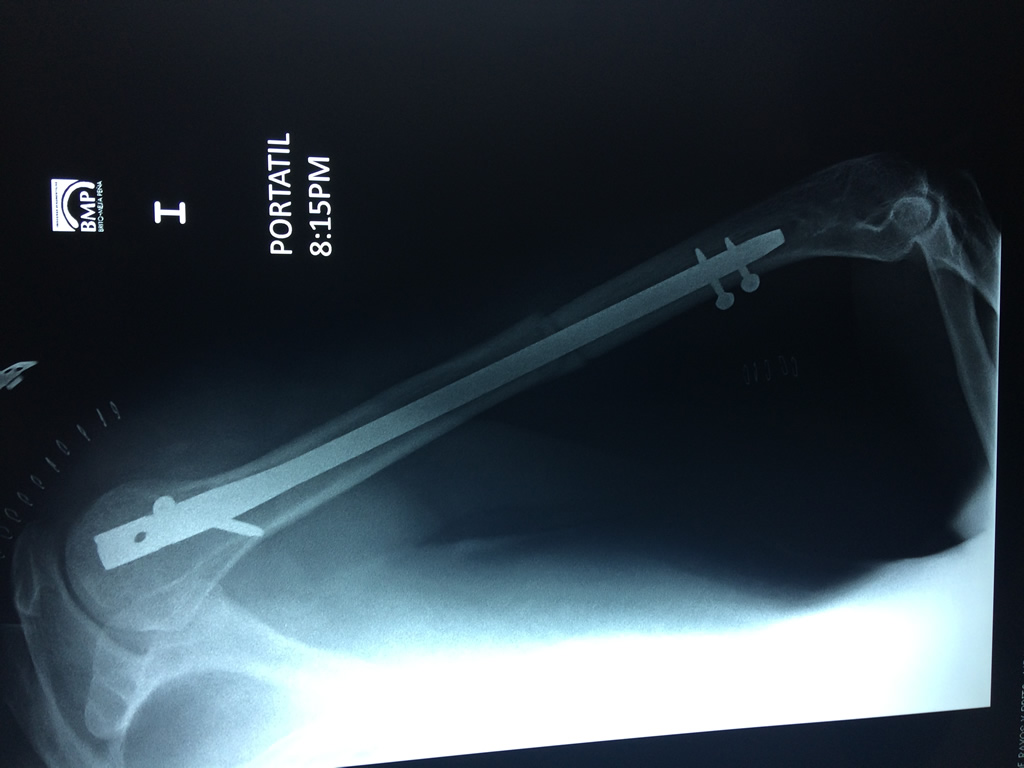

El Húmero (en latín, humerus) es el hueso más largo de las extremidades superiores en el ser humano.  Forma parte del esqueleto apendicular superior y está ubicado en la región del brazo. ... El extremo proximal del húmero tiene la cabeza, cuellos quirúrgico y anatómico y tubérculos mayor y menor.